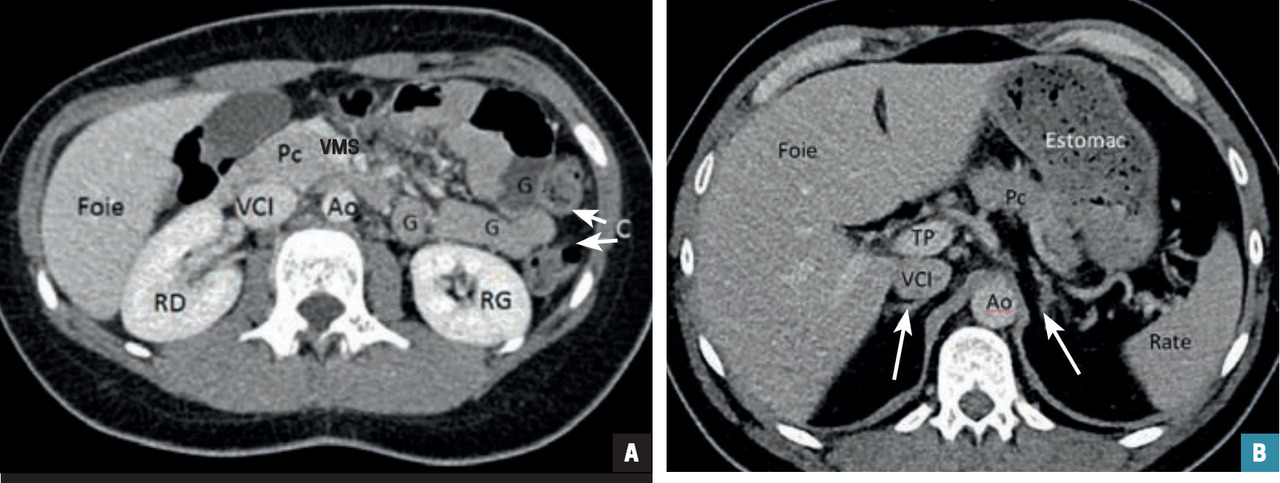

Un patient de 25 ans consulte pour des douleurs abdominales de la fosse iliaque droite. Pas de fièvre, CRP à 15. L’échographie abdominale est normale mais l’appendice n’est pas visible. Le scanner avec injection met en évidence, au temps portal, en arrière du cæcum, une structure tubulée borgne correspondant à l’appendice tuméfié, à paroi épaissie, intensément rehaussé (fig. 2 ; flèche blanche) avec infiltration de la graisse péri-appendiculaire (flèche noire). Le diagnostic d’appendicite aiguë rétro- cæcale est posé. L’échographie a été prise à défaut par la topographie atypique.